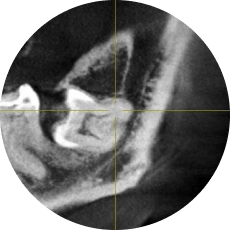

Удаление ретенированных и дистопированных третьих моляров

Что будет в модуле:

Атравматичное удаление ретенированных третьих моляров

Классификация ретенции третьих моляров

Разрезы и типы лоскутов

Техника остеоэктомии

Навыки на уровне челюстно-лицевой хирургии: от удаления зачатка ретенированного нижнего третьего моляра до удаления горизонтально расположенных зубов.